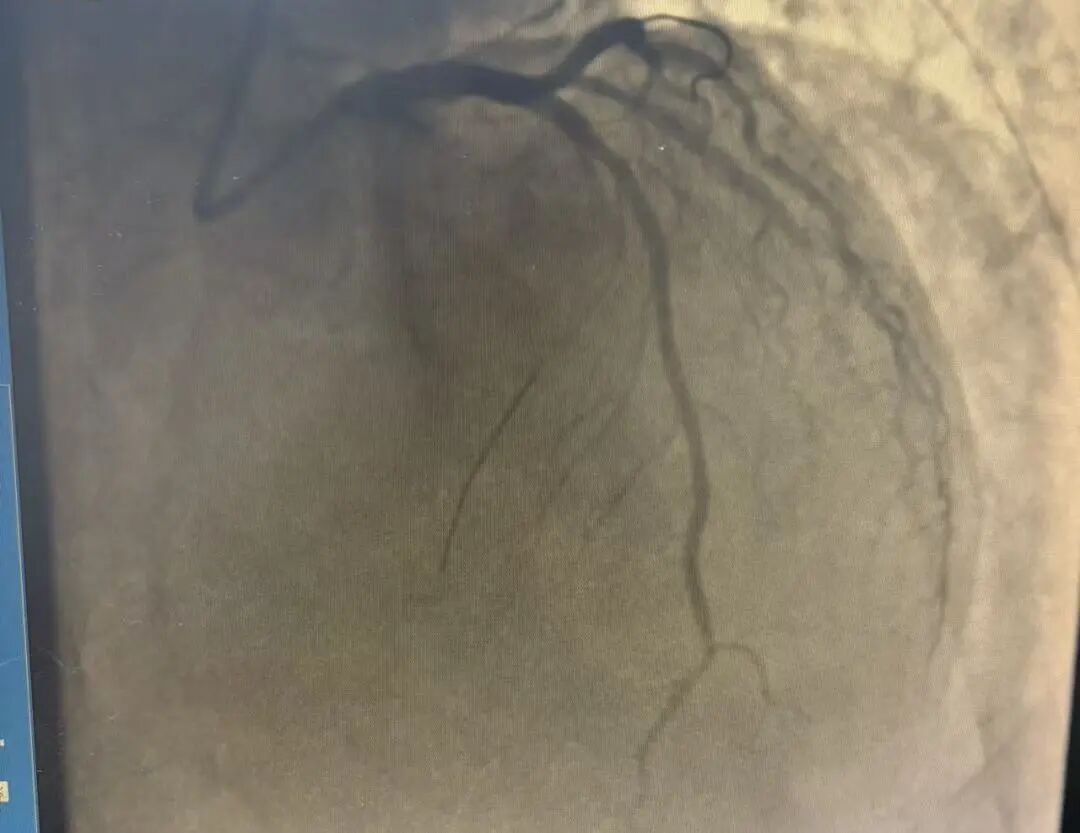

导管室内,冠脉造影屏上触目惊心:左主干本体99%狭窄,前降支血流几乎中断,心肌濒临全面坏死。

冠脉造影(术后)

16:35,术后复查显示,冠脉血流恢复至TIMI 3级,心肌再灌注成功。从患者进入急诊至血管开通,仅用时35分钟,远低于国家胸痛中心90分钟的标准。